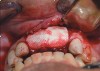

A 45-year-old man who smoked presented in the wake of a blunt trauma to the face. The right lateral incisor had been evulsed, with obvious damage to the facial plate (Figure 11). All other anterior teeth were salvageable.

Reflection of a full-thickness flap revealed complete loss of the facial plate (Figure 12). Approximately 1 cm3 of RegenerOss Allograft Putty was expressed into the defect and molded (Figure 13), then covered with an Ossix Plus membrane (Figure 14). Extensive periosteal-releasing incisions were used in conjunction with mesial- and distal-releasing incisions to obtain passive primary closure.

Figure 11  Blunt trauma to the patient’s face evulsed the right central incisor and damaged the facial plate.

Figure 11

Figure 12  Occlusal view of the lost facial plate after flap reflection.

Figure 12